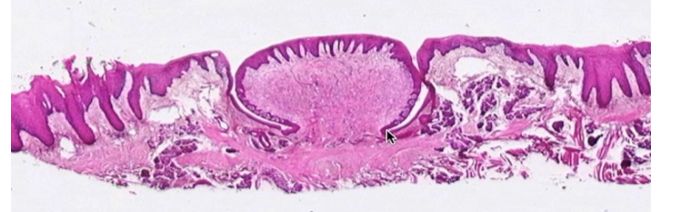

Name this structure

Circumvallate papillae of specialized oral mucosa

Which specialized oral mucosa is surrounded by a moat?

Circumvallate papillae

Which type of specialized oral mucosa divides the anterior 2/3 from the posterior 1/3 of the tongue?